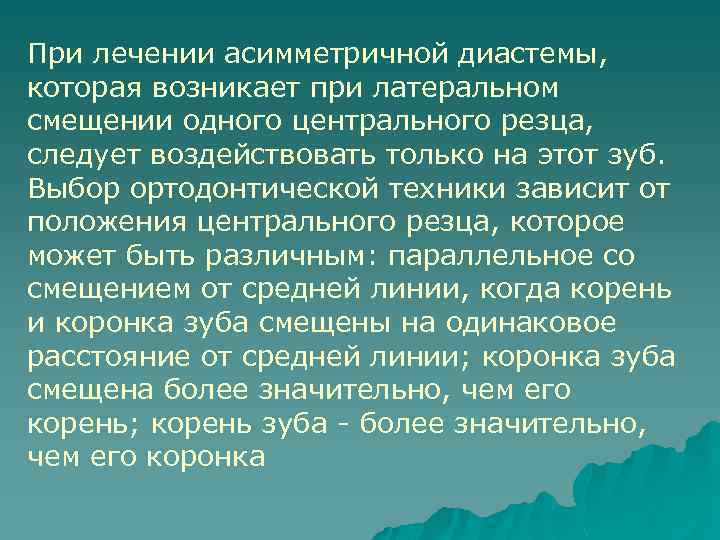

При лечении асимметричной диастемы, которая возникает при латеральном смещении одного центрального резца, следует воздействовать только на этот зуб. Выбор ортодонтической техники зависит от положения центрального резца, которое может быть различным: параллельное со смещением от средней линии, когда корень и коронка зуба смещены на одинаковое расстояние от средней линии; коронка зуба смещена более значительно, чем его корень; корень зуба - более значительно, чем его коронка

Виды ассиметричной диастемы u Параллельное отклонение коронки и корня резца от средней линии u Более значительное перемещение корня резца, чем коронки u Более значительное латеральное перемещение коронки зуба, чем корня u Смещение резца латерально и его тортоаномалия